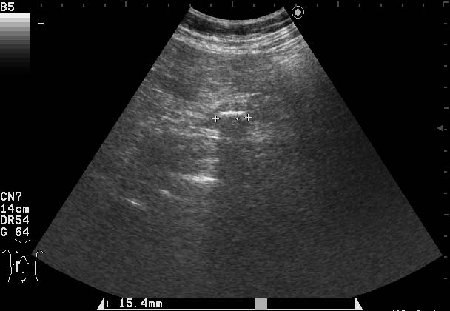

Сонограммы холедоха:

- Поперечный скан холедоха